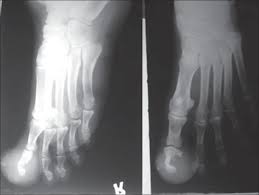

Having a small dark spot under the thumbnail like this needs to be checked out by a doctor as soon as possible. The cancer may look identical to damage caused by injury to the nail, so a person with it may not immediately spot the significance of the nail coloration. This type of melanoma develops equally in all skin colors but represents a greater proportion of. However, look closely at the toe on the right, which is cancerous. At which point the stage, treatment plan, and prognosis are assessed.

Covid Toes Must Know Facts About The Strange Coronavirus Symptom Everyday Health from images.everydayhealth.com This is a good example of a dark brown streak found on the big toe. This type of cancer affects the thumb, index finder, and big toe more often than it strikes any other toe or finger. Extends to involve the skin of the adjacent proximal or lateral nail fold. Another type of skin cancer, basal cell carcinoma, could also cause pearly white bumps on the skin. Becomes more irregular in pigmentation including light brown, dark brown; To me, this looks like a bruise or the result of some damage to the toe or nail, but it is a melanoma. The tumor grows slowly, and can reach a maximum of about 4 cm. It looks like a whitish or yellowish patch that starts at the base of the toenail, near the cuticle.